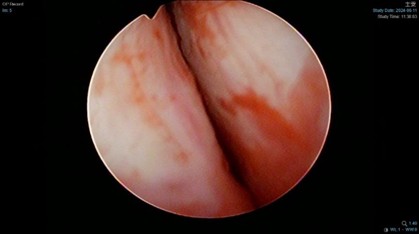

圖(A)肥大的攝護腺壓迫逆尿道開口;圖(B)綠光雷射氣化攝護腺;圖(C)氣化攝護腺後尿道開口重新恢復開闊。